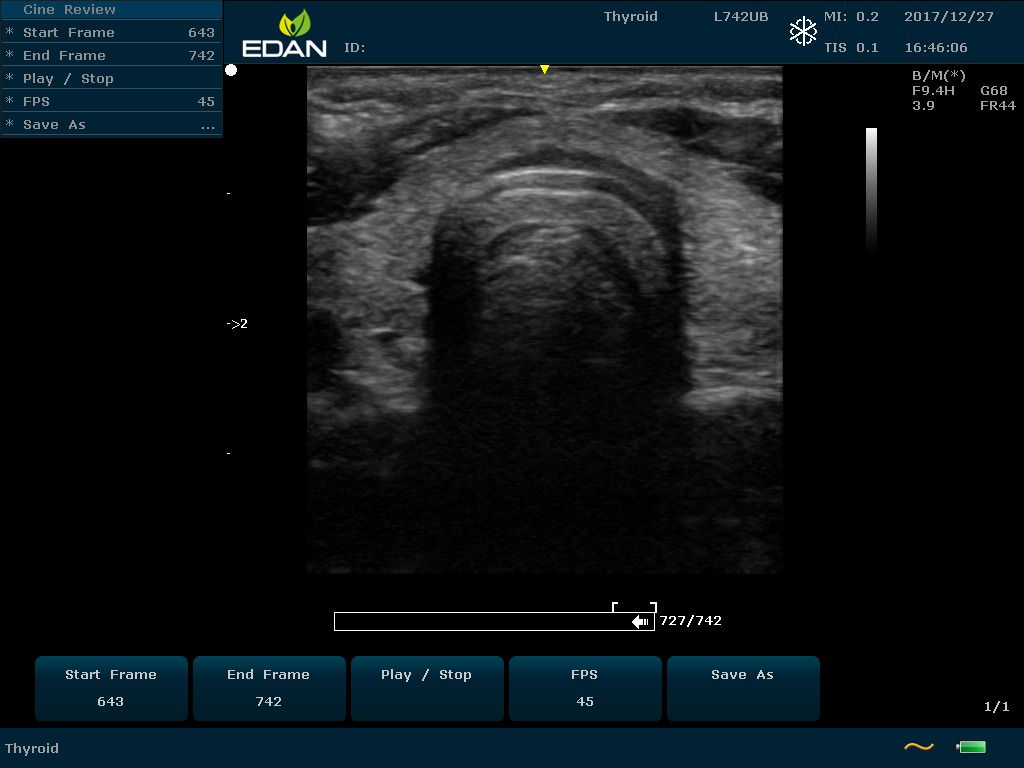

Особенность U60 Edan — расширенное применение. Ультразвуковой аппарат рекомендован для абдоминальных исследований, гинекологии и акушерства, кардиологии, педиатрии, урологии, изучения малых органов, сосудов. Для U60 Edan используются конвексные, линейные, фазированные и внутриполостные датчики.

Передовые технологии позволяют повысить качество визуализации в несколько раз. УЗИ-аппарат U60 Edan отличается возможностью быстрой настройки визуализации. Специальные функции позволяют моментально отображать данные за счет быстрой оптимизации параметров. Режимы визуализации: B-mode, M-mode, Color Doppler, Power Doppler Imaging, Pulsed Wave Doppler, Continuous Doppler.

Для улучшения качества изображений в В-режиме быстро регулируются все необходимые параметры. Быстрые инструменты изображения: LowFlow, Medium Flow, High Flow, Detail, Soft, High Contrast.